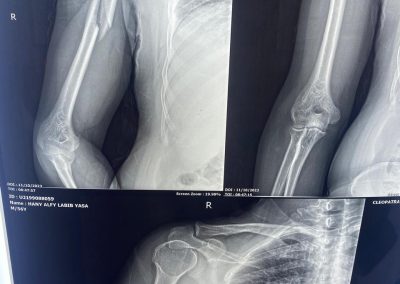

اشعة تبين كسر بالذراع الايمن.